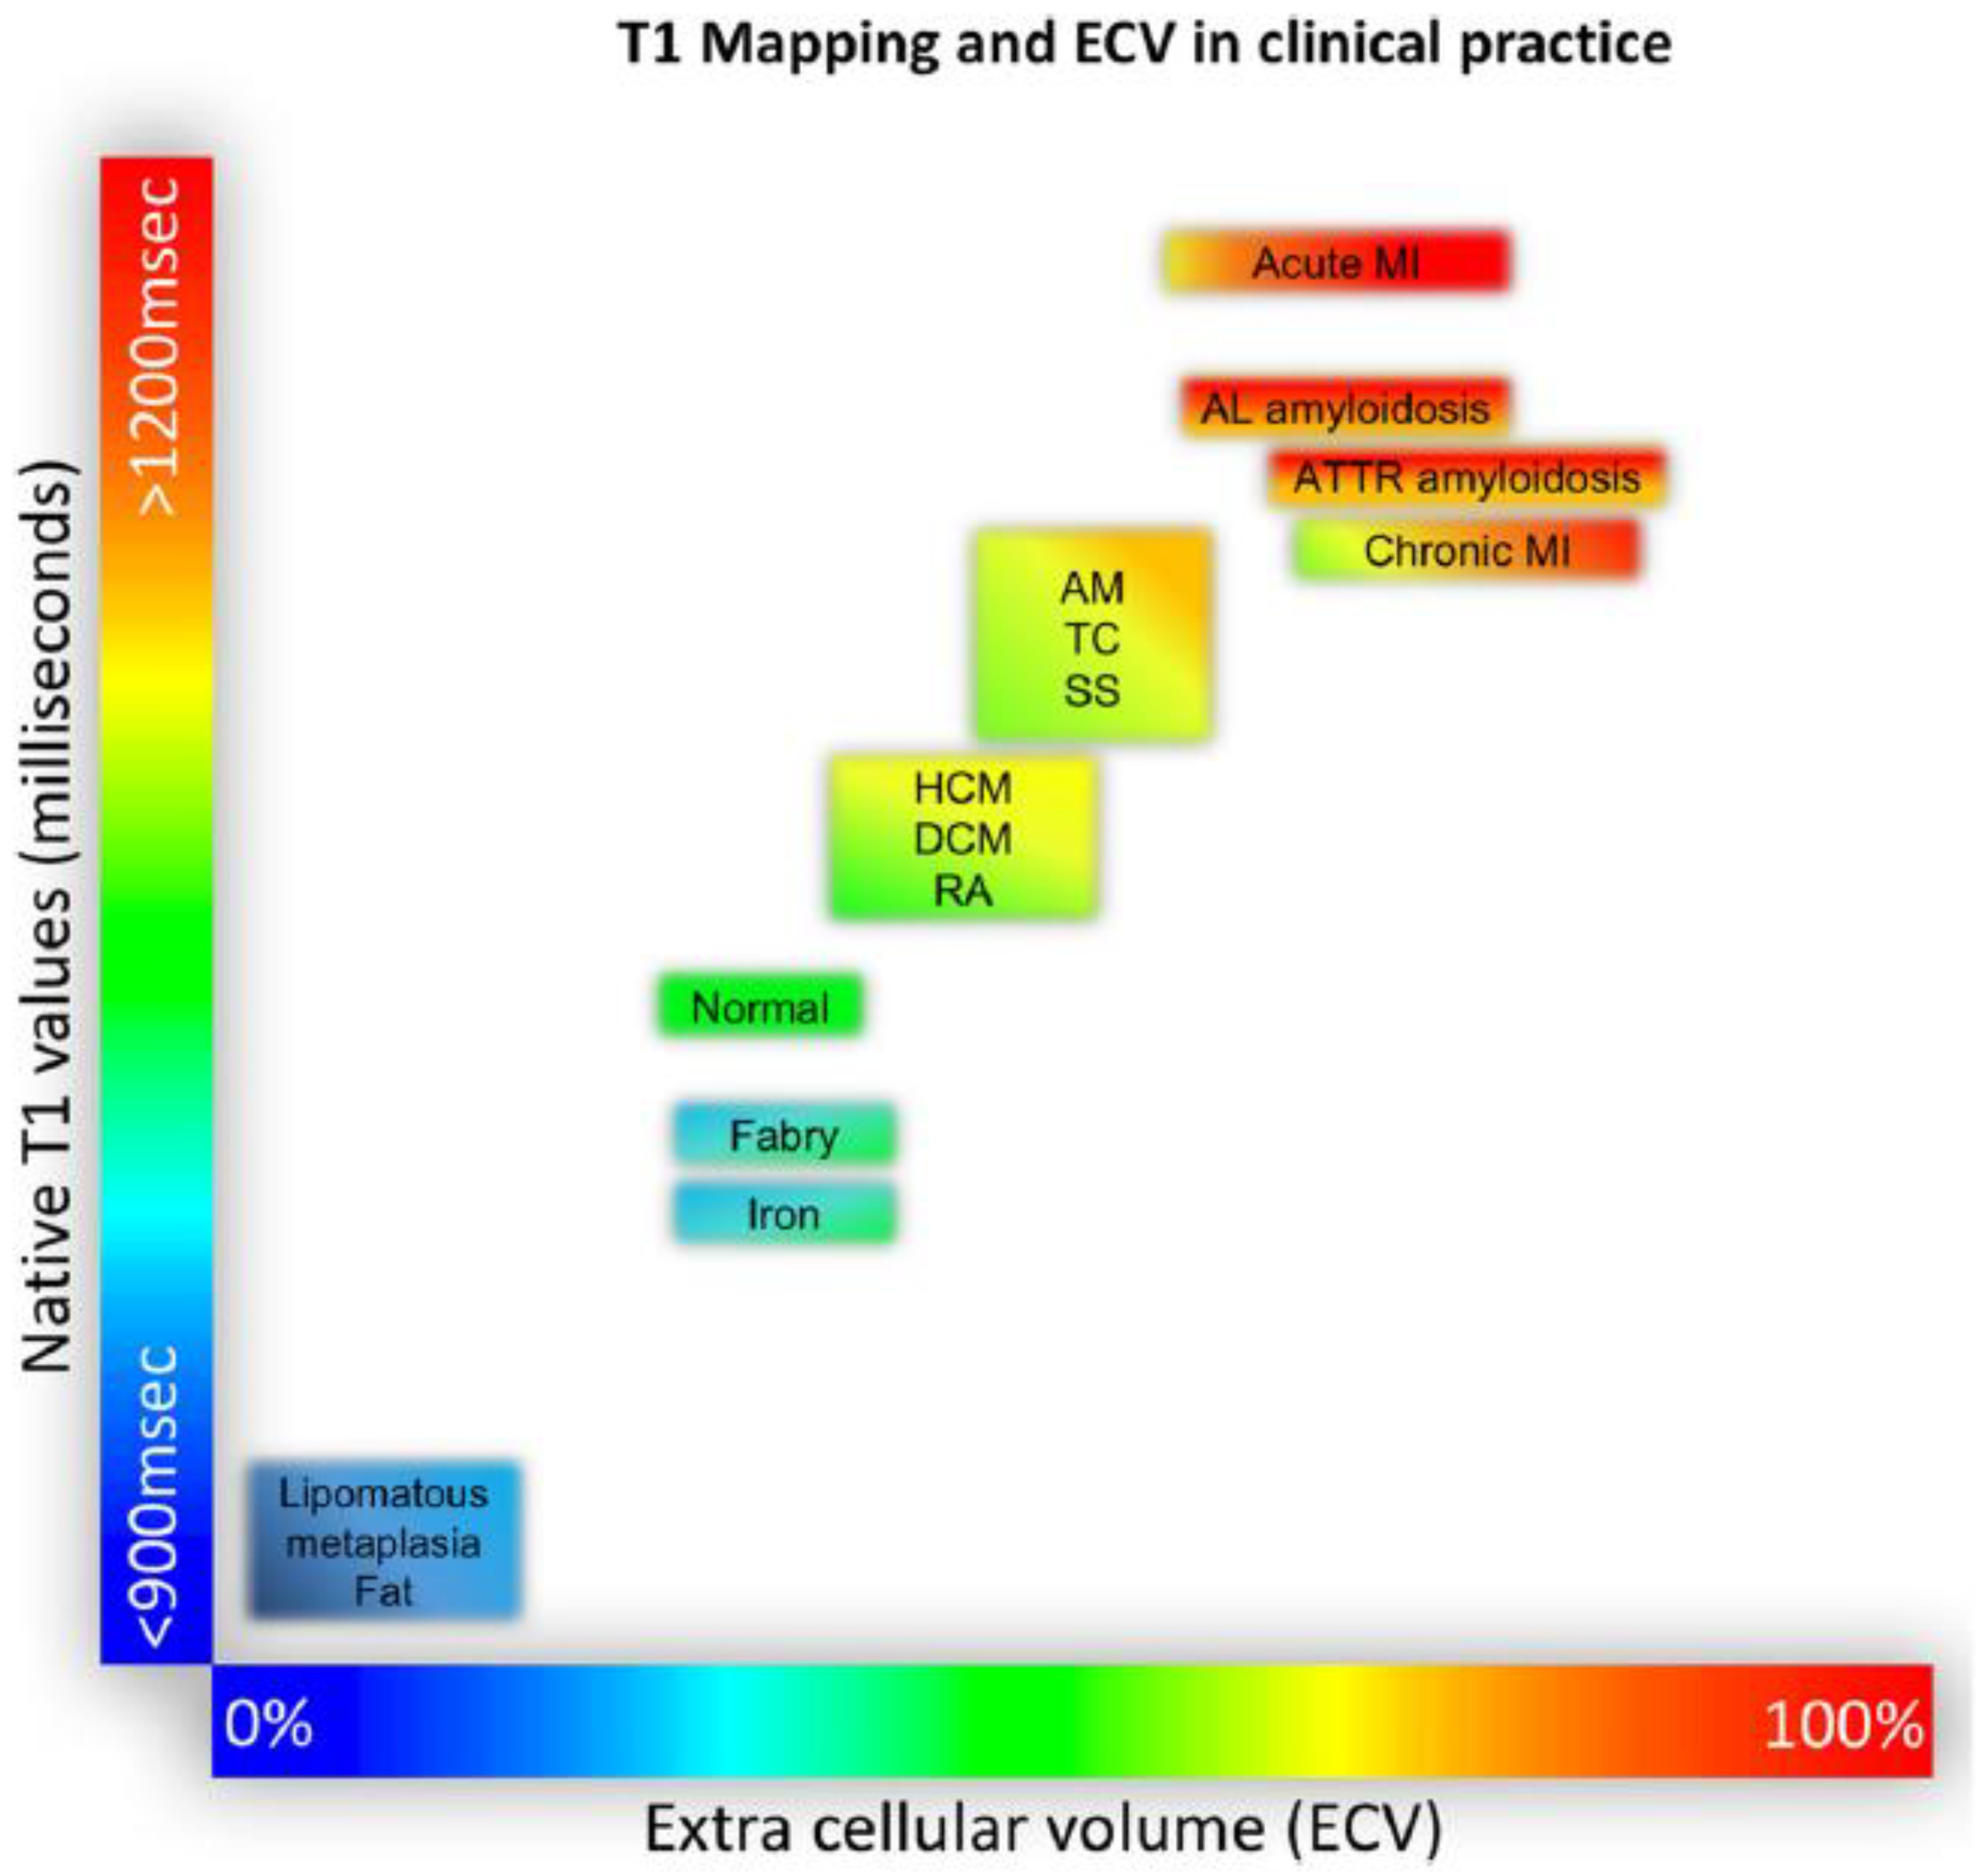

- Pixel-wise maps of the magnetic relaxation parameters T1, T2, and T2*, called “parametric imaging”, allow a limited characterization of underlying tissue ([37]; Figure 5). Additionally, by pre- and post-contrast registration of T1 in the myocardium and blood pool, a direct relative measure of extracellular volume (in percent) for each pixel can be calculated. For example, hemochromatosis leads to shortening and amyloidosis leads to lengthening of T1 relaxation times, which sets these pathologies apart from others. Myocardial edema leads to lengthening of T1 and T2 times and the expansion of extracellular volume, which in themselves are non-specific, but may aid in the diagnosis of, e.g., myocarditis, depending on clinical circumstances. Notably, increased extracellular space may be indicative of diffuse fibrosis but also, e.g., tissue edema. Hence, although, for example, an increased T1 value does correlate modestly with myocardial fibrosis and may, therefore, support the diagnosis of diastolic dysfunction and HFpEF, the relaxation parameters are multifactorial and should not be mistaken for true histology.

- Puntmann, V.O.; Peker, E.; Chandrashekhar, Y.; Nagel, E. T1 Mapping in Characterizing Myocardial Disease: A Comprehensive Review. Circ. Res. 2016, 119, 277–299. [Google Scholar] [CrossRef]

- Messroghli, D.R.; Moon, J.C.; Ferreira, V.M.; Grosse-Wortmann, L.; He, T.; Kellman, P.; Mascherbauer, J.; Nezafat, R.; Salerno, M.; Schelbert, E.B.; et al. Clinical recommendations for cardiovascular magnetic resonance mapping of T1, T2, T2* and extracellular volume: A consensus statement by the Society for Cardiovascular Magnetic Resonance (SCMR) endorsed by the European Association for Cardiovascular Imaging (EACVI). J. Cardiovasc. Magn. Reson. 2017, 19, 75. [Google Scholar]

- Haaf, P.; Garg, P.; Messroghli, D.R.; Broadbent, D.A.; Greenwood, J.P.; Plein, S. Cardiac T1 Mapping and Extracellular Volume (ECV) in clinical practice: A comprehensive review. J. Cardiovasc. Magn. Reson. 2016, 18, 89. [Google Scholar] [CrossRef]